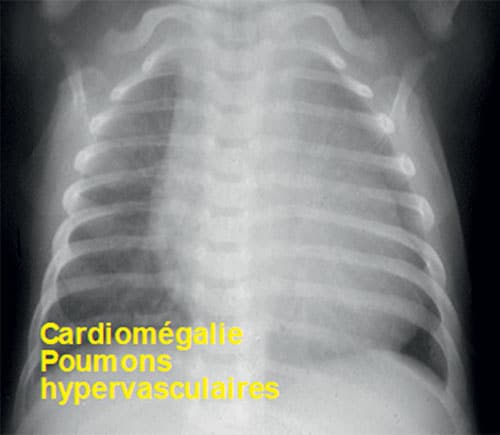

Fig. 11.4 ![]() Radiographie du thorax de face d’un nourrisson porteur d’une très large communication interventriculaire.

Radiographie du thorax de face d’un nourrisson porteur d’une très large communication interventriculaire.

Noter l’importance de la cardiomégalie et de l’hypervascularisation pulmonaire.